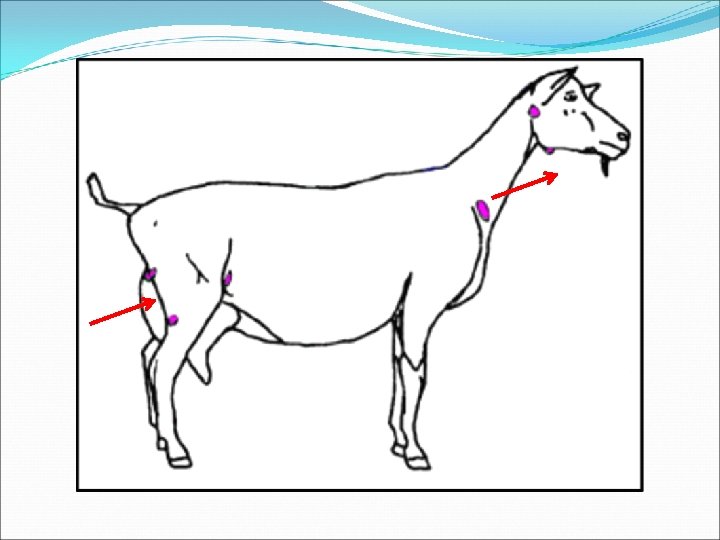

External CLA �Most common form in GOATS �Superficial lymph node abscesses �Diameters of 3 -15 cm �Principal lymph nodes affected �Goats: head & neck � Submandibular, parotid, prescapular �Sheep: torso � #1: Prefemoral, #2: prescapular

Summary of CLA by Species Sheep Goats Most common form Internal External llnn. most affected Torso: Prefemoral Prescapular Head/neck: Submandibular Parotid Prescapular Abscess content Caseated, ‘onion layered’ Uniform, pasty, green